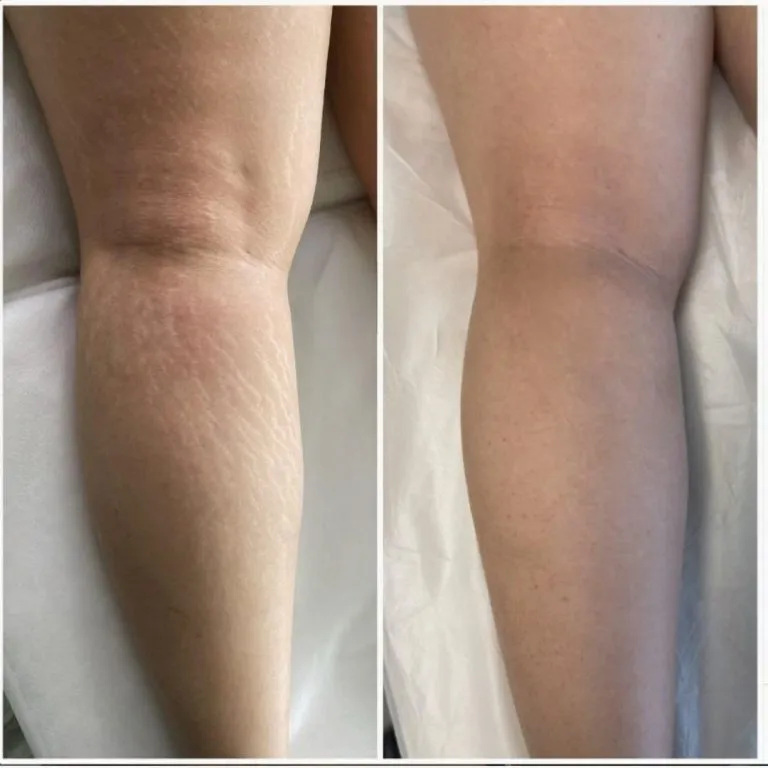

We are a Paramedical Team that uses a natural method to minimize and cover up the appearance of scars. This technique involves using pigments and serums that closely match your skin tone, which are strategically implanted into scarred or discolored areas.